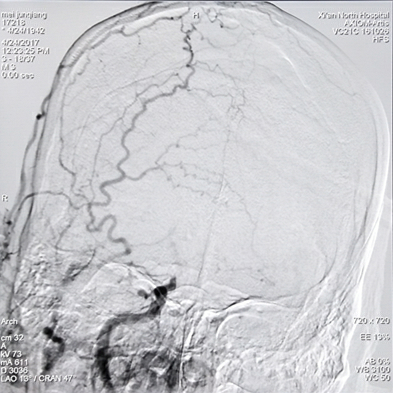

病例二:慢性颈动脉闭塞开通手术

实施颈动脉慢性闭塞开通后颈动脉完美再现,左侧肢体无力症状消失(下图)